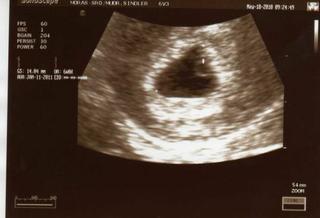

AHojte dievcata! Dlhsie som sa neukazala, mala som depku, ze by aj nas mohol postihnut potrat. Ale vcera sme boli u doktorka a nas drobcek ma 11.7 mm a bije mu srdiecko 😵 😵 😵 Mam aj fotecku va lbumiku. A hrozne sme sa nasmiali u lekara, lebo som sa snazila zistit na monitore, kde ma drobcek hlavicku a rucicky, ... 😀 😀 😀 Tak keby ste nahodou netusili co ta machulka na sone znamena, tak drobec tam visi na pupocnej snure tak sikmo, skoro az dole hlavou 😝 😀

Ahoj baby, tak aj ja sa hlasim, po dlhsom case, chcela som ist k doktorovi na buduci pondelok, ale zvedavost bola silnejsia ako ja , tak som bola dnes, a je to tam, ja sa tak tesiiiiim, doktor to odhaduje na 6tt+0 ale srdiecko este nabolo vidiet, tak mam dojst tak za 10-14 dni, to uz bude isto tlkotat, tak že tak. A mam aj prvu fotečku 😀